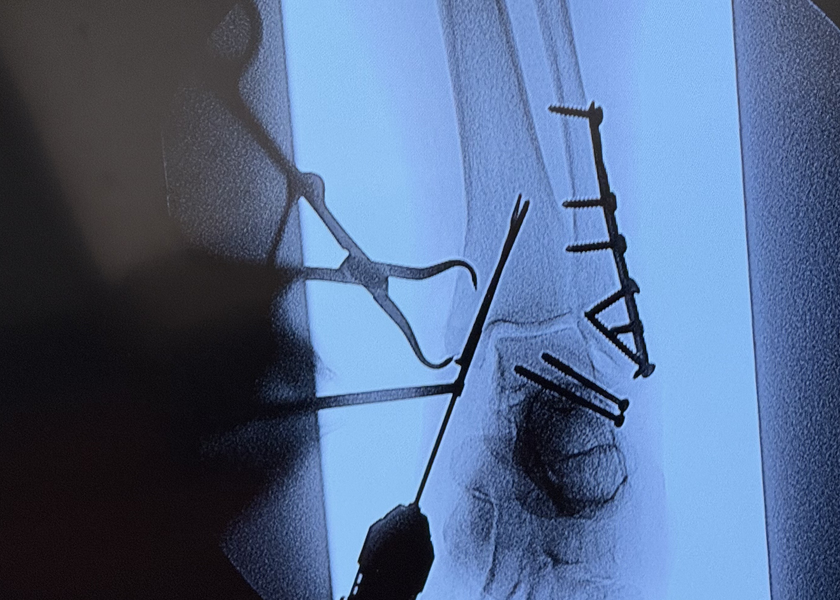

An X-ray of Kelly's leg.

Sometime in the near future, Rockwood may get another horse, but that’s not her focus. She’s set to “finally” get back on her feet, bearing weight, in October. Rockwood had the tib-fib fracture along with a broken ankle. The long time spent crawling created a sizeable wound, and as such, Rockwood has been treated by Nurse Practitioner Amanda Allaire at St. Luke's Clinic - Wound Care: Ketchum.